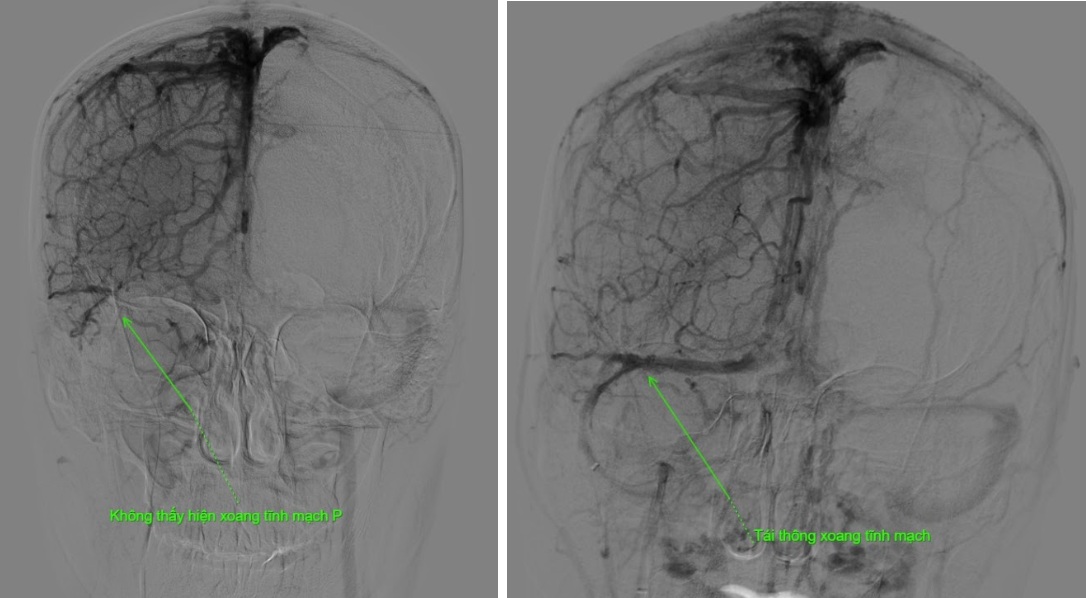

Hình ảnh phim chụp trước và sau can thiệp cho thấy rõ mức độ tắc nghẽn và hiệu quả tái thông sau thủ thuật.

Kết quả phim chụp cho thấy bệnh nhân bị tắc gần như toàn bộ hệ thống tĩnh mạch dẫn lưu não, bao gồm xoang dọc trên, xoang ngang, xoang sigma và đoạn đầu xoang tĩnh mạch cảnh trong phải.

Ca can thiệp kéo dài hơn 2 giờ đồng hồ. Ngay sau thủ thuật, dòng chảy trong hệ thống xoang tĩnh mạch được cải thiện rõ rệt, bệnh nhân giảm nhanh triệu chứng đau đầu và tránh được nguy cơ xuất huyết não, biến chứng nguy hiểm có thể xảy ra nếu xoang tĩnh mạch không được tái thông kịp thời”, Bác sĩ Hải thông tin thêm.